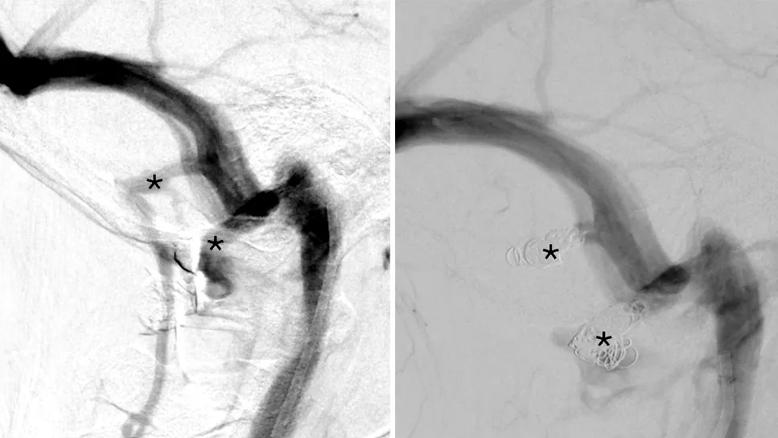

side-by-side scans of a vein in the brain

Case Study: Pulsatile Tinnitus From Emissary Veins Treated With Transvenous Embolization

Innovative approach to the procedure can yield significant relief in complex cases